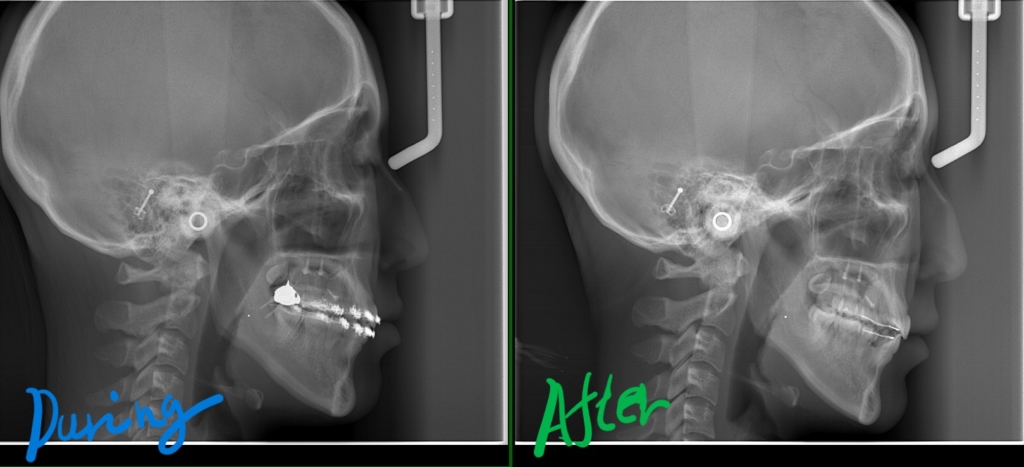

【途中経過】 当初に抜歯をして出来たスペース分は、しっかりと引っ込めることが出来ました。

現状としては、ここまで口元が引っ込みました。

最初と比べてみると、

そこで、アンカースクリューを追加して歯列ごと更に引っ込めることにしました。

最後に、矯正治療前後の「レントゲン写真」と「口元の写真」の比較をお見せしましょう。

それでは、その間の変化をレントゲン写真で見てみましょう。

右側が智歯を抜歯してアンカースクリューを併用しながら歯列全体を引っ込めた後の状態、

歯列の途中の奥歯を抜歯するほどには変化させられませんが、智歯という普通は抜歯だけで済ませる歯を利用することで、このように「もう一声!」口元の変化を起こすことも可能です。